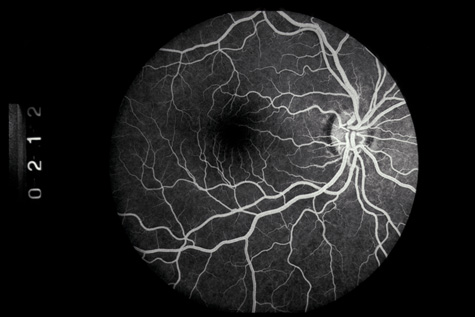

Commotio retinae (Latin, meaning retinal contusion) is a contrecoup injury. It can occur peripherally (Fig. 8) or centrally, in which case it is called Berlin's edema (Fig. 9). Immediately and for several hours after the trauma, the retina appears normal, although the patient may complain of decreased vision. Thereafter, the outer layers of affected retina become opaque. On fluorescein angiography, the opaque retina blocks background choroidal fluorescence, and in most cases there is no leakage into or under the retina (Fig. 10). For years, clinicians had difficulty explaining this blockage, because leakage is expected in conditions with edema. It was then shown in experimental animals and in human autopsy eyes that Berlin's edema is not true edema. The retinal opaqueness is the result of intracellular edema and fragmentation of the photoreceptor outer segments and intracellular edema of the underlying pigment epithelium. There is little or no intercellular fluid.66–69

Fig. 10. A: Commotio retinae in the macula. B: On the angiogram there is no leakage in the area of commotio retinae.